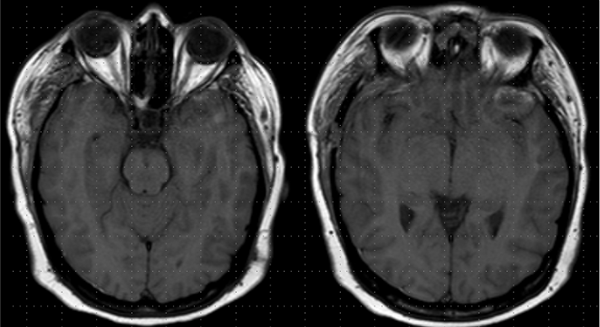

La paciente fue sometida a cirugía de exéresis por abordaje subfrontal, logrando resección macroscópica completa cuyo resultado histopatológico fue quiste de la bolsa de Rathke (Figuras 6 y 7). Evolucionando posteriormente con GOS 5, pupilas reflécticas, con mejoría campimétrica. Movilizándose espontáneamente sin déficit motor ni sensitivo. Sin cefalea, sin vómitos ni convulsiones. Sin fistula de LCR. Afebril. Presentando diabetes insípida que se trata con desmopresina 0,3 mg/dia; con lo que normaliza ionograma, densidad urinaria y osmolaridad plasmática. Alcanzando así el alta hospitalaria.

Figura 6: RM cortes axiales en T1 evidenciando ausencia de lesión tumoral.

Figura 7: RM T1 con gadolinio cortes sagital y coronal que evidencian ausencia de lesión tumoral.